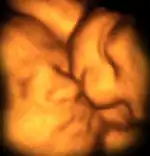

Близнята у матці. Зображення отримали за допомогою ультразвуку